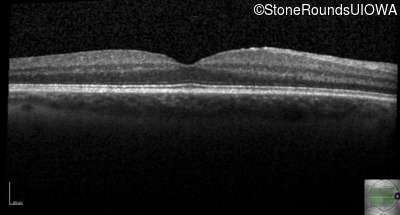

Optical Coherence Tomography - Right - 20/20

Exemplar / OCT Stack

Optical Coherence Tomography - Left - 20/20 -2